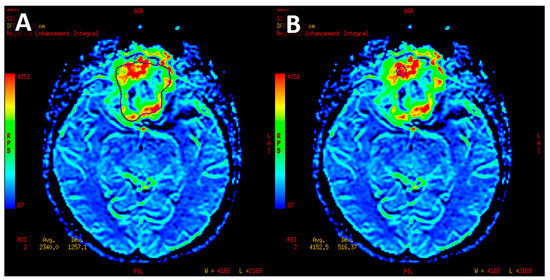

- Mean perfusion parameters for the whole tumor (labeled as rCBV’1)—the arithmetic mean of the perfusion values collected by outlining the tumor with ROIs on each axial slice (Figure 4A).

- Mean of maximum perfusion parameters (labeled as rCBV’2)—the arithmetic mean of the maximum perfusion values collected by outlining the regions with the highest values with circular ROIs (about 30–60 mm2) on each axial slice of the tumor (Figure 4B).

- Maximum perfusion values (labeled as rCBV’3)—the maximum values collected from the whole tumor with a circular ROI (about 30 mm2–60 mm2) (Figure 4B).